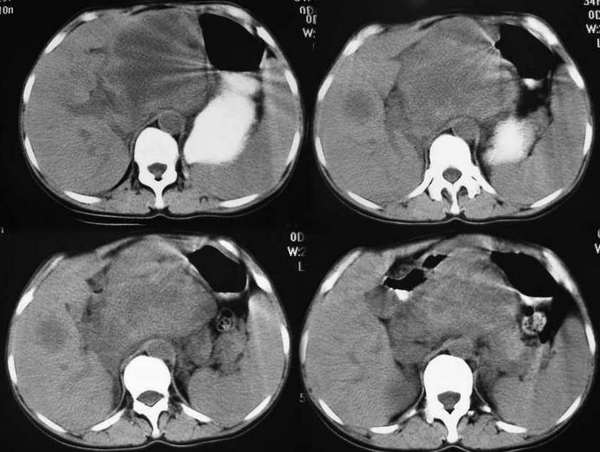

以下是引用东北在2006-1-20 15:36:00的发言:[br]图象少 外生性肝癌并肝内转移侵犯胃窦[br]胰腺的图象少

以下是引用wangqj1976在2006-1-20 21:11:00的发言:[br]不支持胰腺癌的诊断[br]1位置抬高,病变在腹腔干之上, 2胆管、胆囊主胰管不扩张,化验胆红素不高。[br]不支持肝癌[br]1无乙肝、肝硬化病史2病变强化方式[br]支持胃癌可能性大,合并肝转移、胰腺受累。(病人还贫血)[br]脾大,可以用肿瘤压迫脾静脉来解释。[br]建议做上消化道钡餐检查。